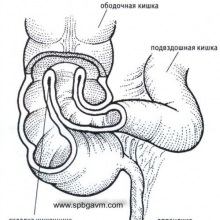

Intussusceptio bél - a bevezetése a bélből a következő rész azonos belekben. Intussusceptio az eredménye egy erős csökkenése a bélfal. Végrehajtása bél szegmenst nevezik intussusceptum. Intussusceptio rendszerint a különféle betegségekben a gyomor-bél traktus, például ka.